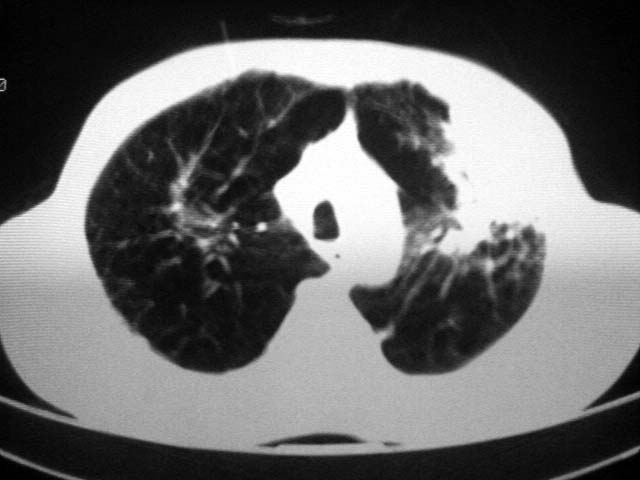

以下是引用zjzjr在2007-9-4 17:00:00的发言:[br]双上肺继发型结核伴左上肺空洞形成.慢性支气管炎伴肺气肿.

以下是引用liuzheng_9326在2007-9-4 16:23:00的发言:[br]痰检未见结核菌, 治疗后症状好转。图像符合陈旧性结核伴感染。